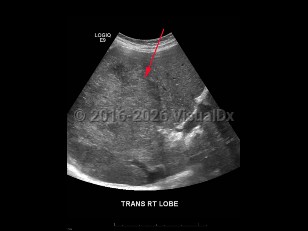

Imaging Studies image of Hepatocellular carcinoma - imageId=8358911. Click to open in gallery.  caption: '<span>Grayscale ultrasound image of the liver demonstrating a heterogeneously hyperechoic mass in the right lobe of the liver. Pathology proven hepatocellular carcinoma.</span>'

Grayscale ultrasound image of the liver demonstrating a heterogeneously hyperechoic mass in the right lobe of the liver. Pathology proven hepatocellular carcinoma.